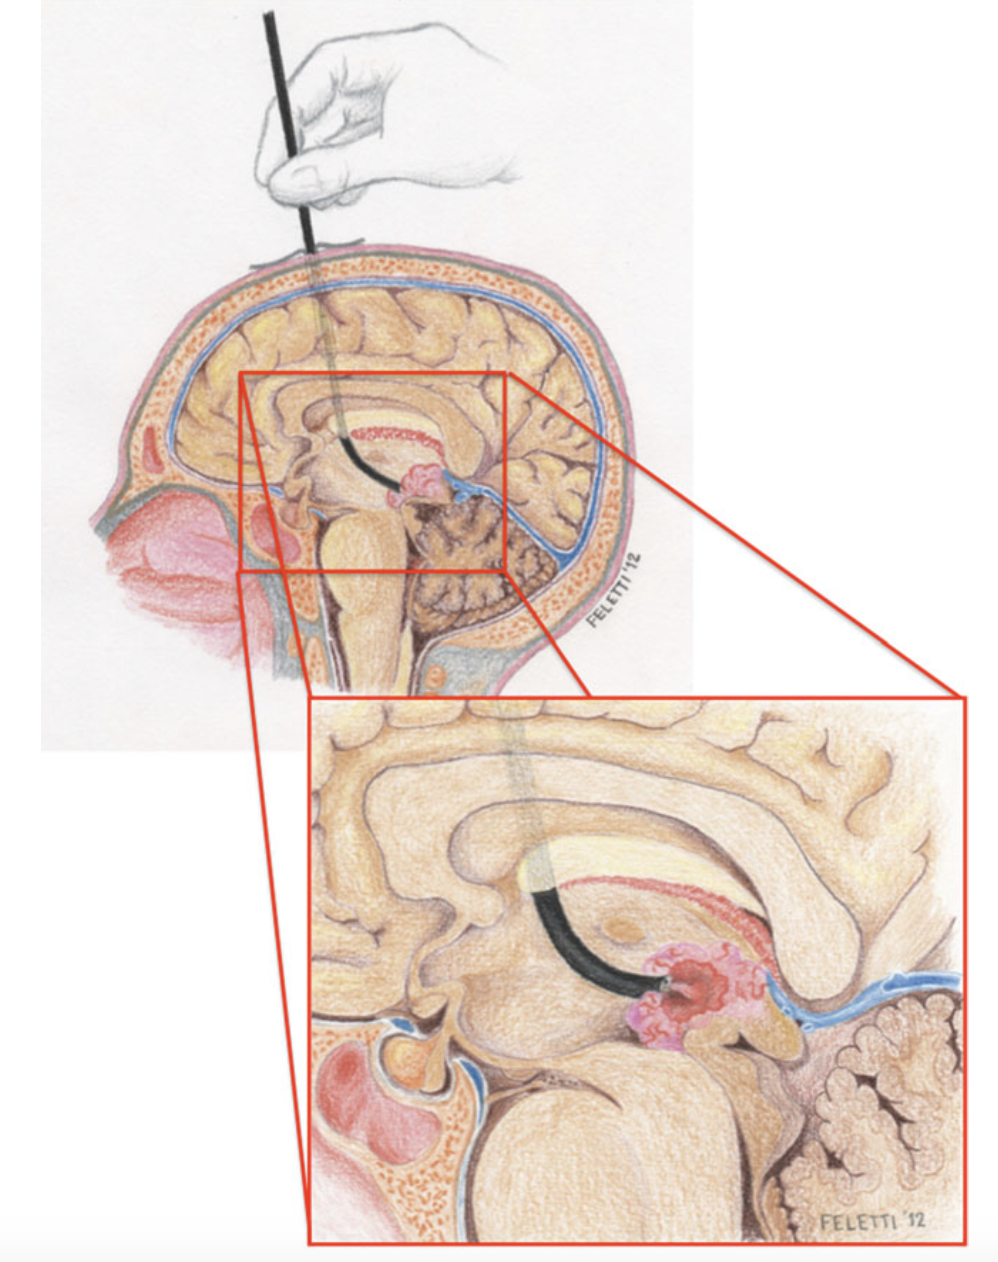

Neurochirurgo presso l'Azienda Ospedaliero-Universitaria Integrata di Verona, ha eseguito circa 3.000 interventi neurochirurgici, di cui oltre 2.000 come primo operatore. Affianca all'attività clinica un impegno costante nella ricerca e nella didattica universitaria. È autore di oltre 100 pubblicazioni peer-reviewed e 10 capitoli di libro, illustratore anatomico per pubblicazioni scientifiche ed Associate Editor di Frontiers in Surgery — Neurosurgery. Ha maturato esperienze di ricerca e cliniche all'estero, tra cui l'Università della California a San Francisco (UCSF), la Fujita Health University (Nagoya) e la Fudan University (Shanghai).

I suoi interessi chirurgici principali comprendono la chirurgia vertebrale, la chirurgia cerebrovascolare, i tumori cerebrali, i tumori intramidollari, la neuroendoscopia e la neurochirurgia funzionale. È inoltre titolare di un brevetto per un elettrodo di neuromonitoraggio in ambito endoscopico (brevetto italiano ed europeo).